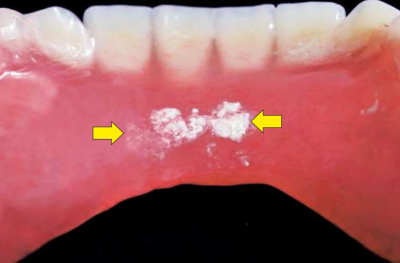

下顎全部床義歯の写真を別に示す。矢印で示す付着物を義歯用ブラシで洗浄したが、ほとんど除去できなかった。

除去法として適切なのはどれか。1つ選べ。

a. 酸溶液への浸漬

b. 中性洗剤溶液への浸漬

c. 水を用いた超音波洗浄

d. サンドブラスターの使用

e. スチームクリーナーの使用